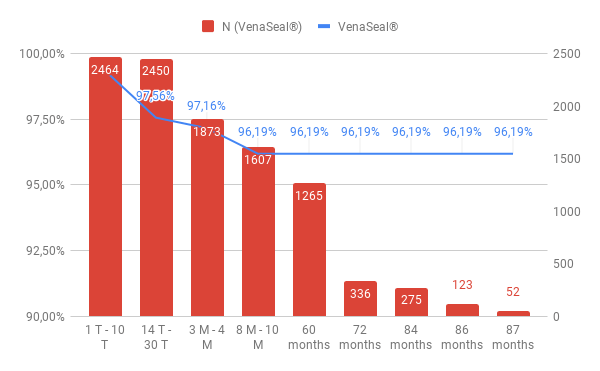

SaphenionScience: 87 months veinglue on 2464 truncal varicose veins: Our results

Duplex control follow up over 86 months: the first day 2464 veins were re-examined. 2448 veins were sealed initially = 99,35% closure rate.

After 14 – 30 days we found 48 partial and 12 completely recanalized veins able to follow up of 2454 sealed truncal veins (99,50%) = 97,55% closure rate.

Three to four months post operationem we had 50 partial and 20 complete recanalisations able to follow up 1873 veins (76 %) = 97,16% closure rate.

After eight to ten months we observed 59 partial and 35 complete recanalisations able to follow up 1607 veins (65,2%) = 96,19% closure rate.

No further recanalisations were found after 87 months up to now! The closure rate over all the time of 87 months = 96,19%.